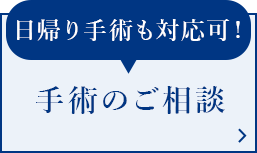

視野のゆがみ、中心暗点、視力低下、コントラスト低下といった症状をきたし、見え方が低下します。現在、加齢黄斑変性は、国内の視覚障害者手帳交付の原因疾患において第4位にある病気です。すでに欧米先進国では成人(特に50歳以上)の中途失明の主要原因疾患になっており、生活習慣の欧米化が進む日本でも、加齢黄斑変性の患者数は増加傾向にあります。

変視症

見たい部分がゆがんで見えます。